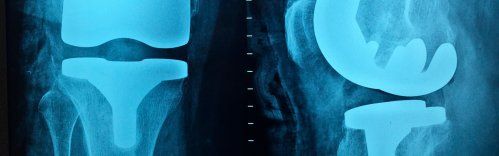

Somos especialistas en la implantación de prótesis de cadera y rodilla, brindando soluciones personalizadas para recuperar la funcionalidad y mejorar la calidad de vida.[...]